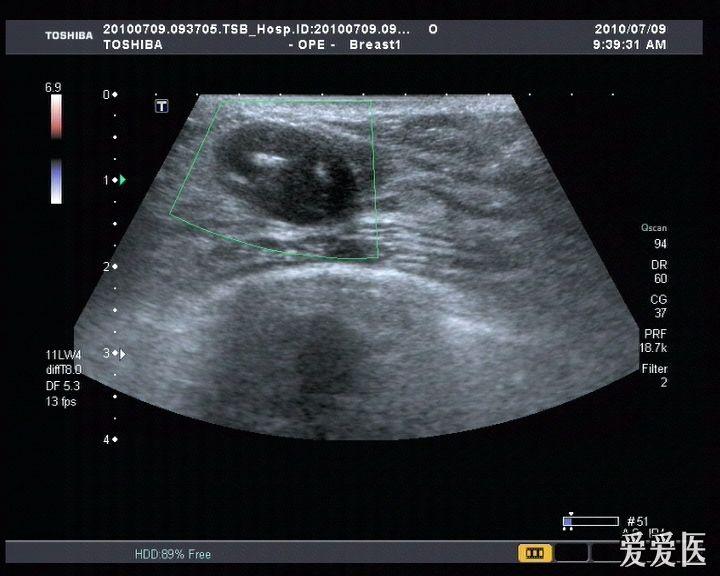

乳腺纤维腺瘤超声

【讨论】乳腺纤维瘤 - 超声医学讨论版 - 爱爱医医学论坛

乳腺纤维瘤? - 超声医学讨论版 - 爱爱医医学论坛